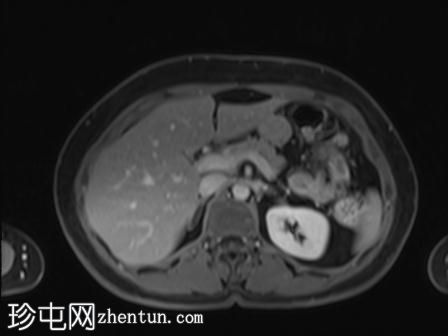

轴位

T2加权像

可见局部晚期浸润性内生型宫颈癌,肿瘤大小为30 x 32 x 48 mm。该肿瘤已侵犯宫颈前唇和后唇的深层间质,以及子宫肌层的下段。

此外,肿瘤还累及宫旁组织。影像学检查发现异常淋巴结肿大,最大短轴直径(SAD)为10 mm,位于髂总血管分叉处和髂内动脉链下方。该淋巴结肿大在弥散加权成像(DWI)上显示水限制,且增强扫描后可见强化。

宫内节育器(IUD)位于子宫内正常位置。左侧子宫底壁内肌瘤大小为15 x 16 mm(FIGO 4期)。子宫内膜厚度约为3 mm,未见宫腔内病变。双侧卵巢外观正常,未见实性或囊性病变。